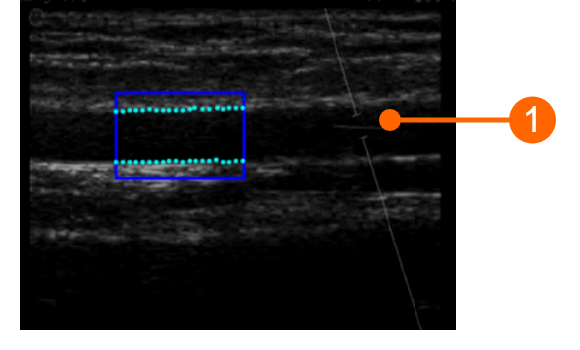

L'angle entre le faisceau Doppler et l'orientation du vaisseau doit être ≤60 degrés. Le volume de l'échantillon doit être aussi large que possible mais sans englober les parois du vaisseau et permettre une légère marge d'erreur en cas de mouvement. Faites attention que le curseur du volume d'échantillon doppler n'est pas dans le ROI où le diamètre est calculé. Il est recommandé que le volume de l'échantillon soit de 5 à 15 mm en dehors de la ROI.

images/download/attachments/381258618/cvs_setupDuplex_bmode_gliffy-version-1-modificationdate-1759328517224-api-v2.png

ATTENTION : faites attention à ce que rien d'autre que l'image échographique ne soit dans la ROI. Veuillez noter que le traitement peut être affecté par des annotations ou tout autre objet graphique qui se superpose à l'image. En particulier, faites attention à ce que le curseur du volume d'échantillon Doppler ne se trouve pas dans la ROI.

La ROI du flux Doppler doit couvrir toute l'étendue du profil de flux Doppler. L'axe de débit nul (2) doit être inclus dans la ROI : il sera automatiquement reconnu et tracé en jaune. L'axe vertical (3) doit être extérieur à la ROI. Veuillez également vous assurer que toute annotation (4) est en dehors de la ROI car elle pourrait affecter l'analyse du flux.